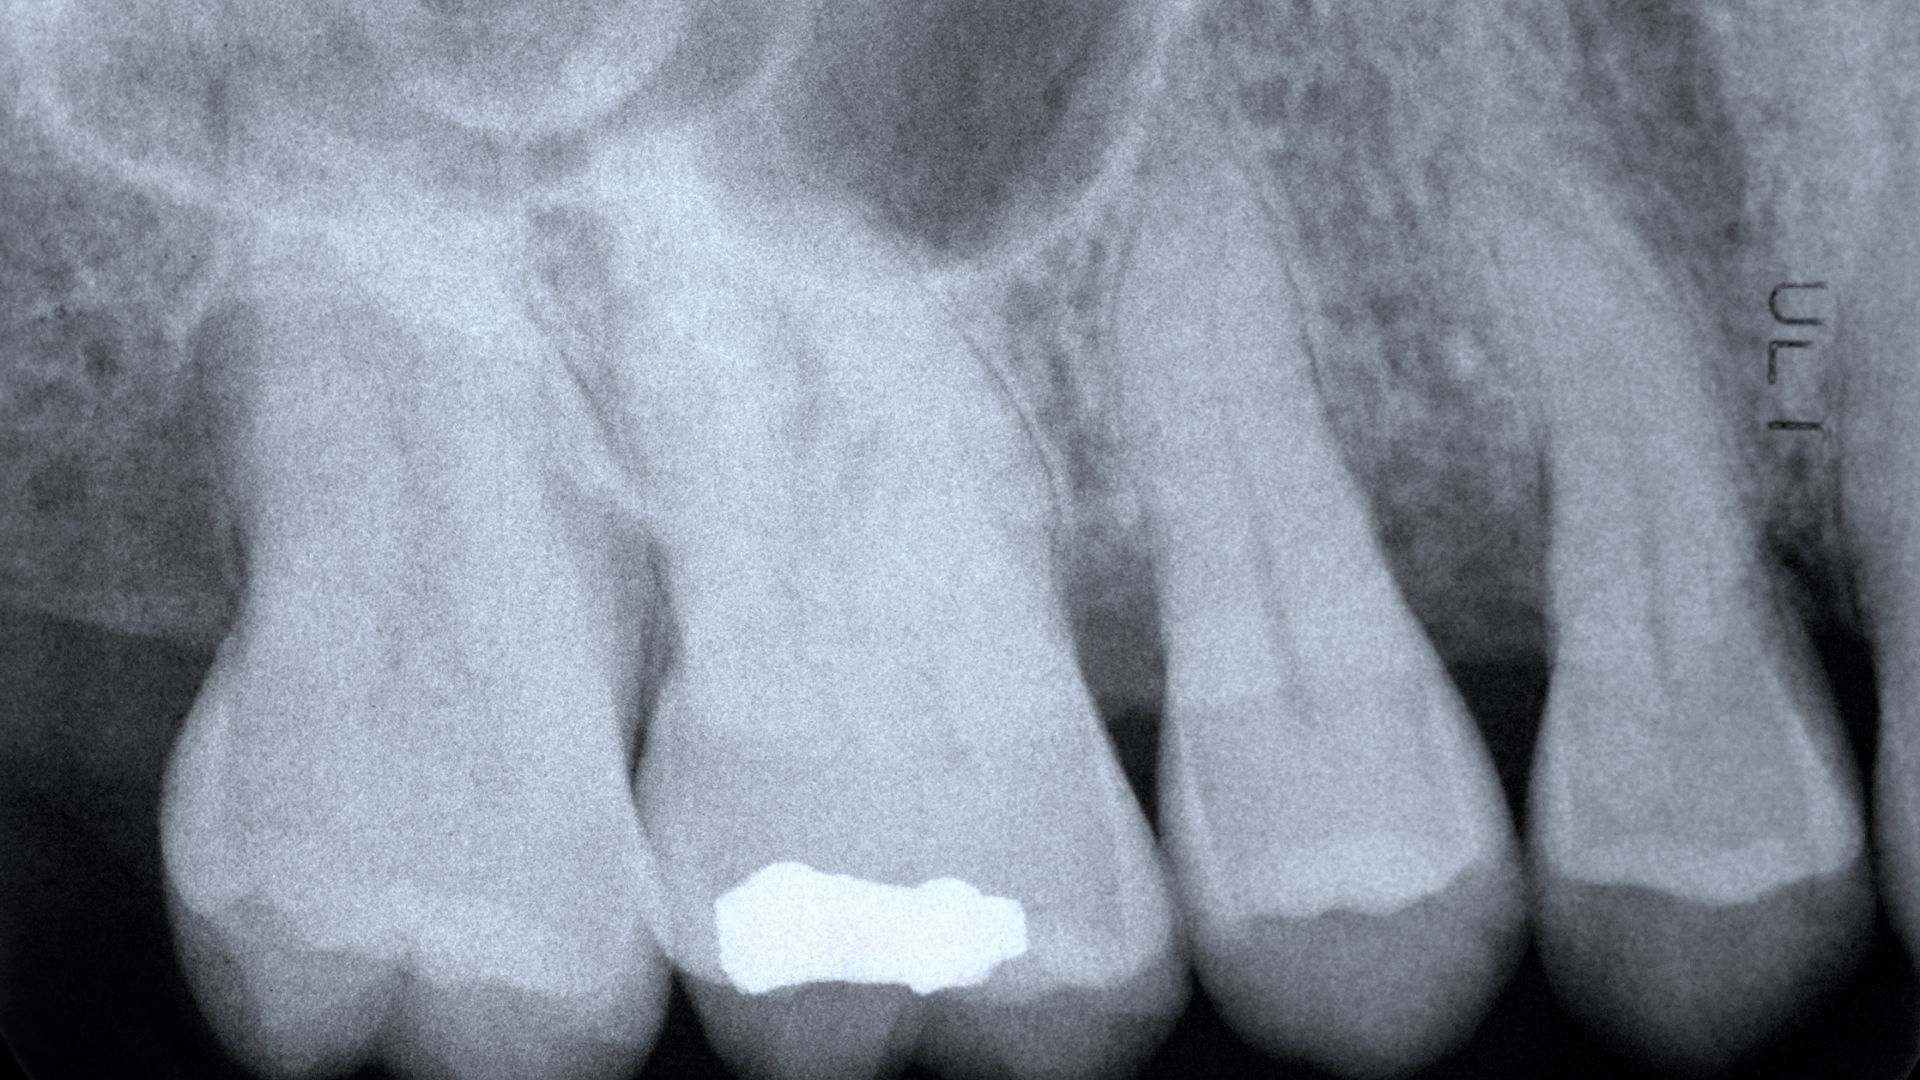

Đây là kỹ thuật loại bỏ phần tủy bị viêm hoặc hoại tử, làm sạch ống tủy rồi trám bít kín để ngăn vi khuẩn tái xâm nhập. Quy trình điều trị thường gồm các bước:

- Thăm khám và chụp X-quang xác định vị trí viêm.

- Gây tê cục bộ và mở buồng tủy.

- Loại bỏ mô tủy bệnh lý, làm sạch ống tủy.

- Trám bít ống tủy bằng vật liệu chuyên dụng.

- Cuối cùng, phục hồi thân răng bằng miếng trám hoặc mão sứ.

Điều trị đúng kỹ thuật giúp răng vẫn hoạt động bình thường mà không còn đau. Tỷ lệ bảo tồn răng thật có thể đạt đến 90% nếu được điều trị kịp thời.